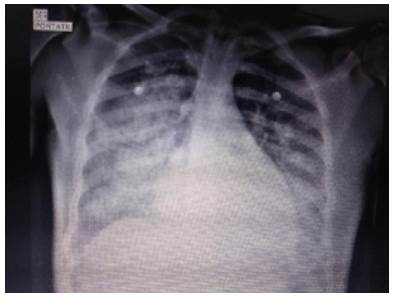

Chest x-ray showed bilateral alveolar opacities from the hilum towards the pleura in the lower two thirds of both lung fields, without images compatible with pleural effusion (Figure 1).

Chest x-ray.

Figure 1: Chest x-ray.

Source: Document obtained during the conduct of the study.